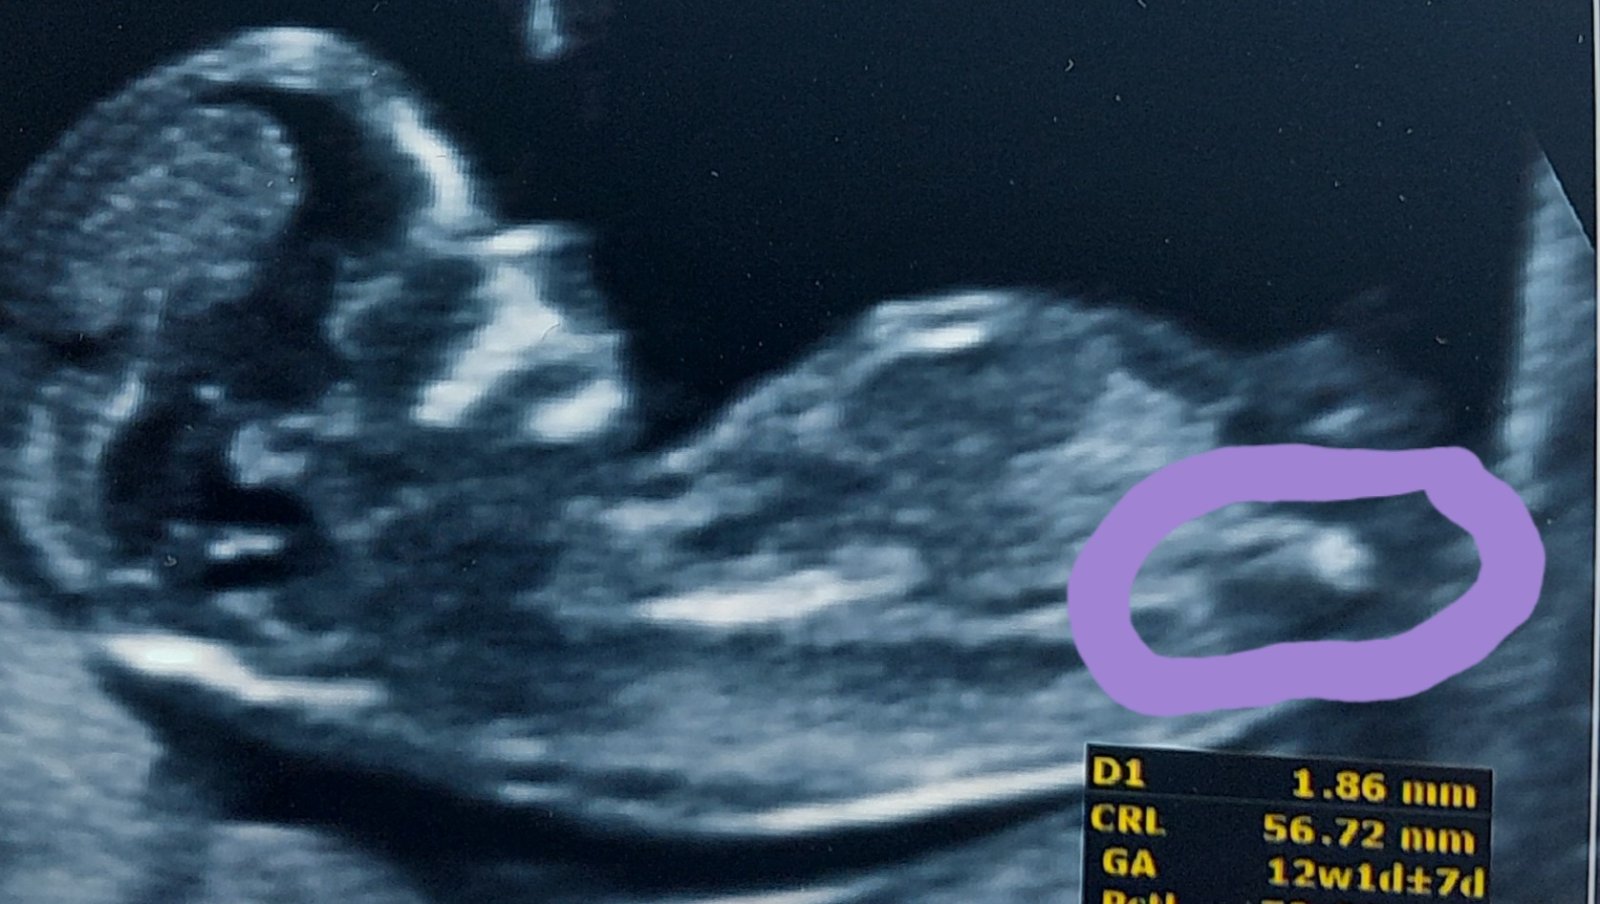

Holčička nebo chlapeček? Výsledky screeningu a tip lékaře.

Pockala bych na druhy screening 🙂 navíc mi přijde, ze to co mas v kroužku není totéž co na druhé fotce.